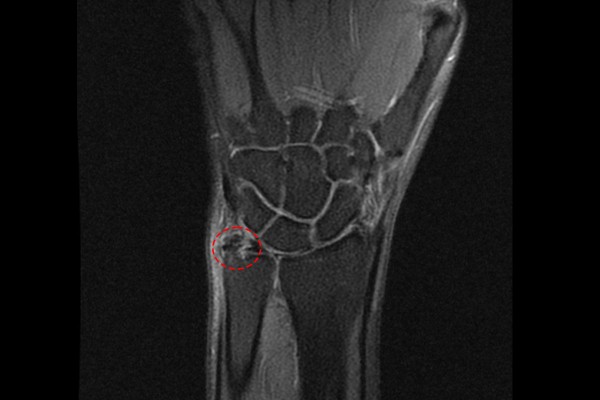

자세한 확인 및 다른 연부조직의 이상유무를 확인하기 위해 MRI 검사를 시행하였고, MRI에서도 역시 석회가 확인되어 손목 석회성 힘줄염(Calcific tendinitis wrist Lt)을 진단하였습니다.